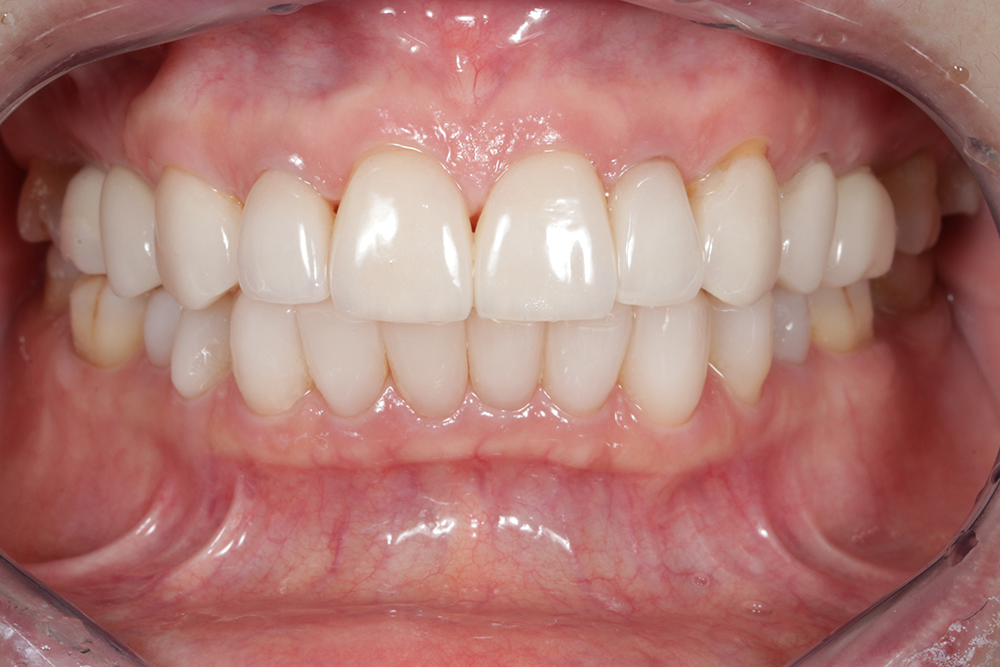

Cas 2

Dr Francesca Vailati – Alignement corrigé (ortho), dents blanchies, amélioration de l’état gingival